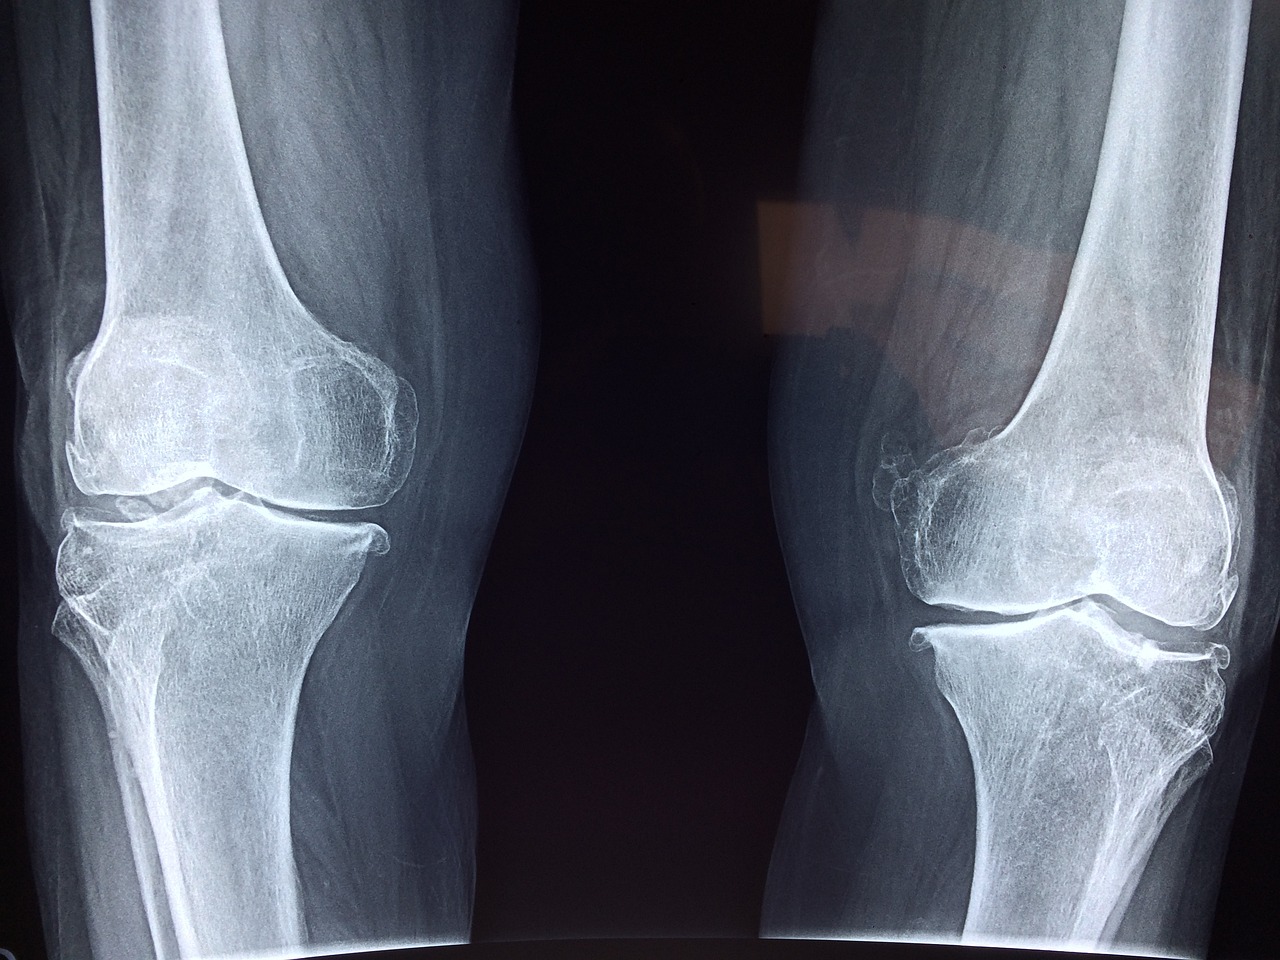

골다공증은 뼈가 약해지고 쉽게 부러지기 쉬운 상태로, 나이가 들면서 자연스럽게 발생하는 현상이지만 칼슘 섭취가 부족하거나 불균형한 식습관을 가질 경우 그 위험이 더욱 높아집니다. 특히, 여성의 경우 폐경 이후 에스트로겐 분비 감소로 인해 골밀도가 급격히 떨어지기 때문에 충분한 칼슘 섭취가 필수적입니다.

칼슘이 뼈 건강에 중요한 이유는 뼈의 지속적인 재형성 과정에 관여하기 때문입니다. 뼈는 파골세포가 오래된 뼈를 제거하고 조골세포가 새로운 뼈를 생성하는 과정을 반복하며 유지됩니다. 이 과정에서 칼슘이 부족하면 새로운 뼈 형성이 원활하지 않게 되어 골밀도가 낮아지고 골다공증 위험이 증가합니다.